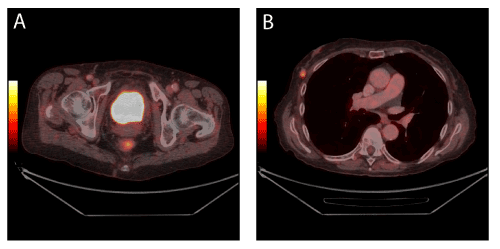

| Figure 1: Muscle invasive bladder cancer in a 78-year-old patient. The bladder tumour is not visible on axial 18F-FDG PET/CT images due to urinary excretion of 18F-FDG which mask the tumour. No metastases from the bladder tumour were demonstrated. However, a mass suspicious for malignancy was demonstrated in the right breast as can be seen on axial fused PET/CT images (1B). Histology confirmed a primary breast cancer. |